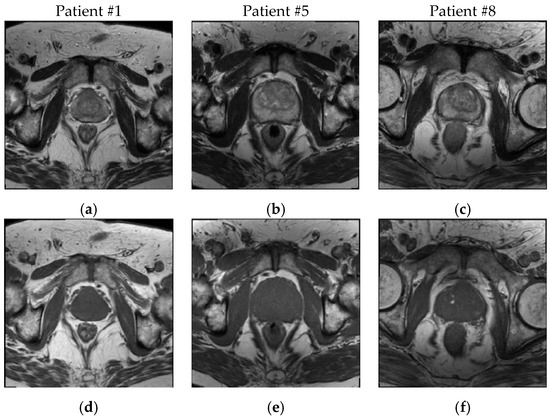

3.1. Patient Dataset Description

3.2.1. MR Image Co-Registration